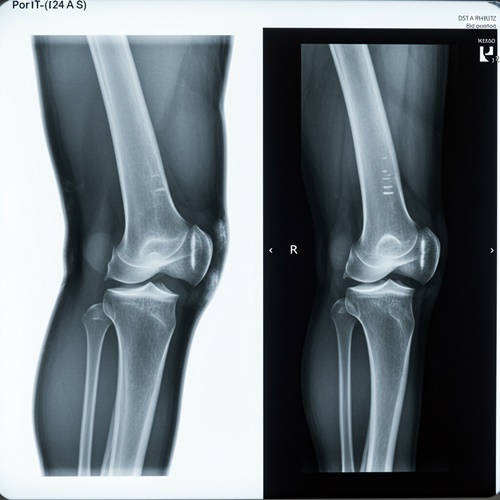

1기는 자각 증상이 거의 없거나 간헐적인 불편함 정도로, 무릎에 약간의 뻣뻣함이 느껴지고 운동 후에만 통증이 있는 경우가 많아요. 이 시기는 엑스레이 검사에서도 큰 이상이 나타나지 않을 수 있어요. 반면, 2기에는 통증이 점점 자주 발생하고, 무릎을 꺾거나 움직일 때 소리가 나거나 저림 증상까지 동반될 수 있어요. 이 단계부터는 엑스레이 상에서 연골의 마모와 관절 간격 감소가 관찰돼요. 무릎 관절염 증상을 이 시점에서 인지하고 적절한 조치를 취하는 것이, 이후 진행을 막는 중요한 전환점이 돼요.

무릎 관절염은 보통 4단계로 구분돼요. 1기는 통증이 거의 없거나 일시적인 수준이고, 2기에는 일상생활 중 통증과 뻣뻣함이 발생해요. 3기부터는 연골 손상이 명확해지고, 4기는 연골이 거의 닳아 관절 간격이 사라지며 극심한 통증과 기능 저하가 나타나요. 무릎 관절염 증상이 반복되고 악화된다면 빠른 진단과 대처가 필요해요.

| 단계 | 주요 증상 및 특징 | X-ray 소견 | 일상생활 영향 |

| 1기 | 거의 통증 없음 또는 가벼운 불편감, 간헐적 뻣뻣함 | 정상 혹은 미세한 연골 마모 | 활동에는 큰 지장 없음 |

| 2기 | 통증 자주 발생, 무릎이 뻣뻣하고 가끔 붓는 느낌 | 관절 간격 약간 좁아짐, 초기 연골 마모 | 계단 오르내릴 때 불편, 오래 걷기 힘듦 |

| 3기 | 지속적인 통증, 무릎을 굽히기 어려움, 마찰음 발생 | 연골 손상 뚜렷, 관절 간격 현저히 좁아짐 | 일상 동작에 제약, 걷기나 일어서기 어려움 |

| 4기 | 극심한 통증, 무릎 변형, 기능 저하 | 관절 간격 거의 소실, 뼈끼리 맞닿음 | 정상적인 보행 어려움, 수술 고려 가능 성 |